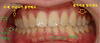

상하악 후퇴 --> 어긋난 어금니 --> 통증 (31세) 작성자 김동오 작성시간 25.11.06 조회수 39